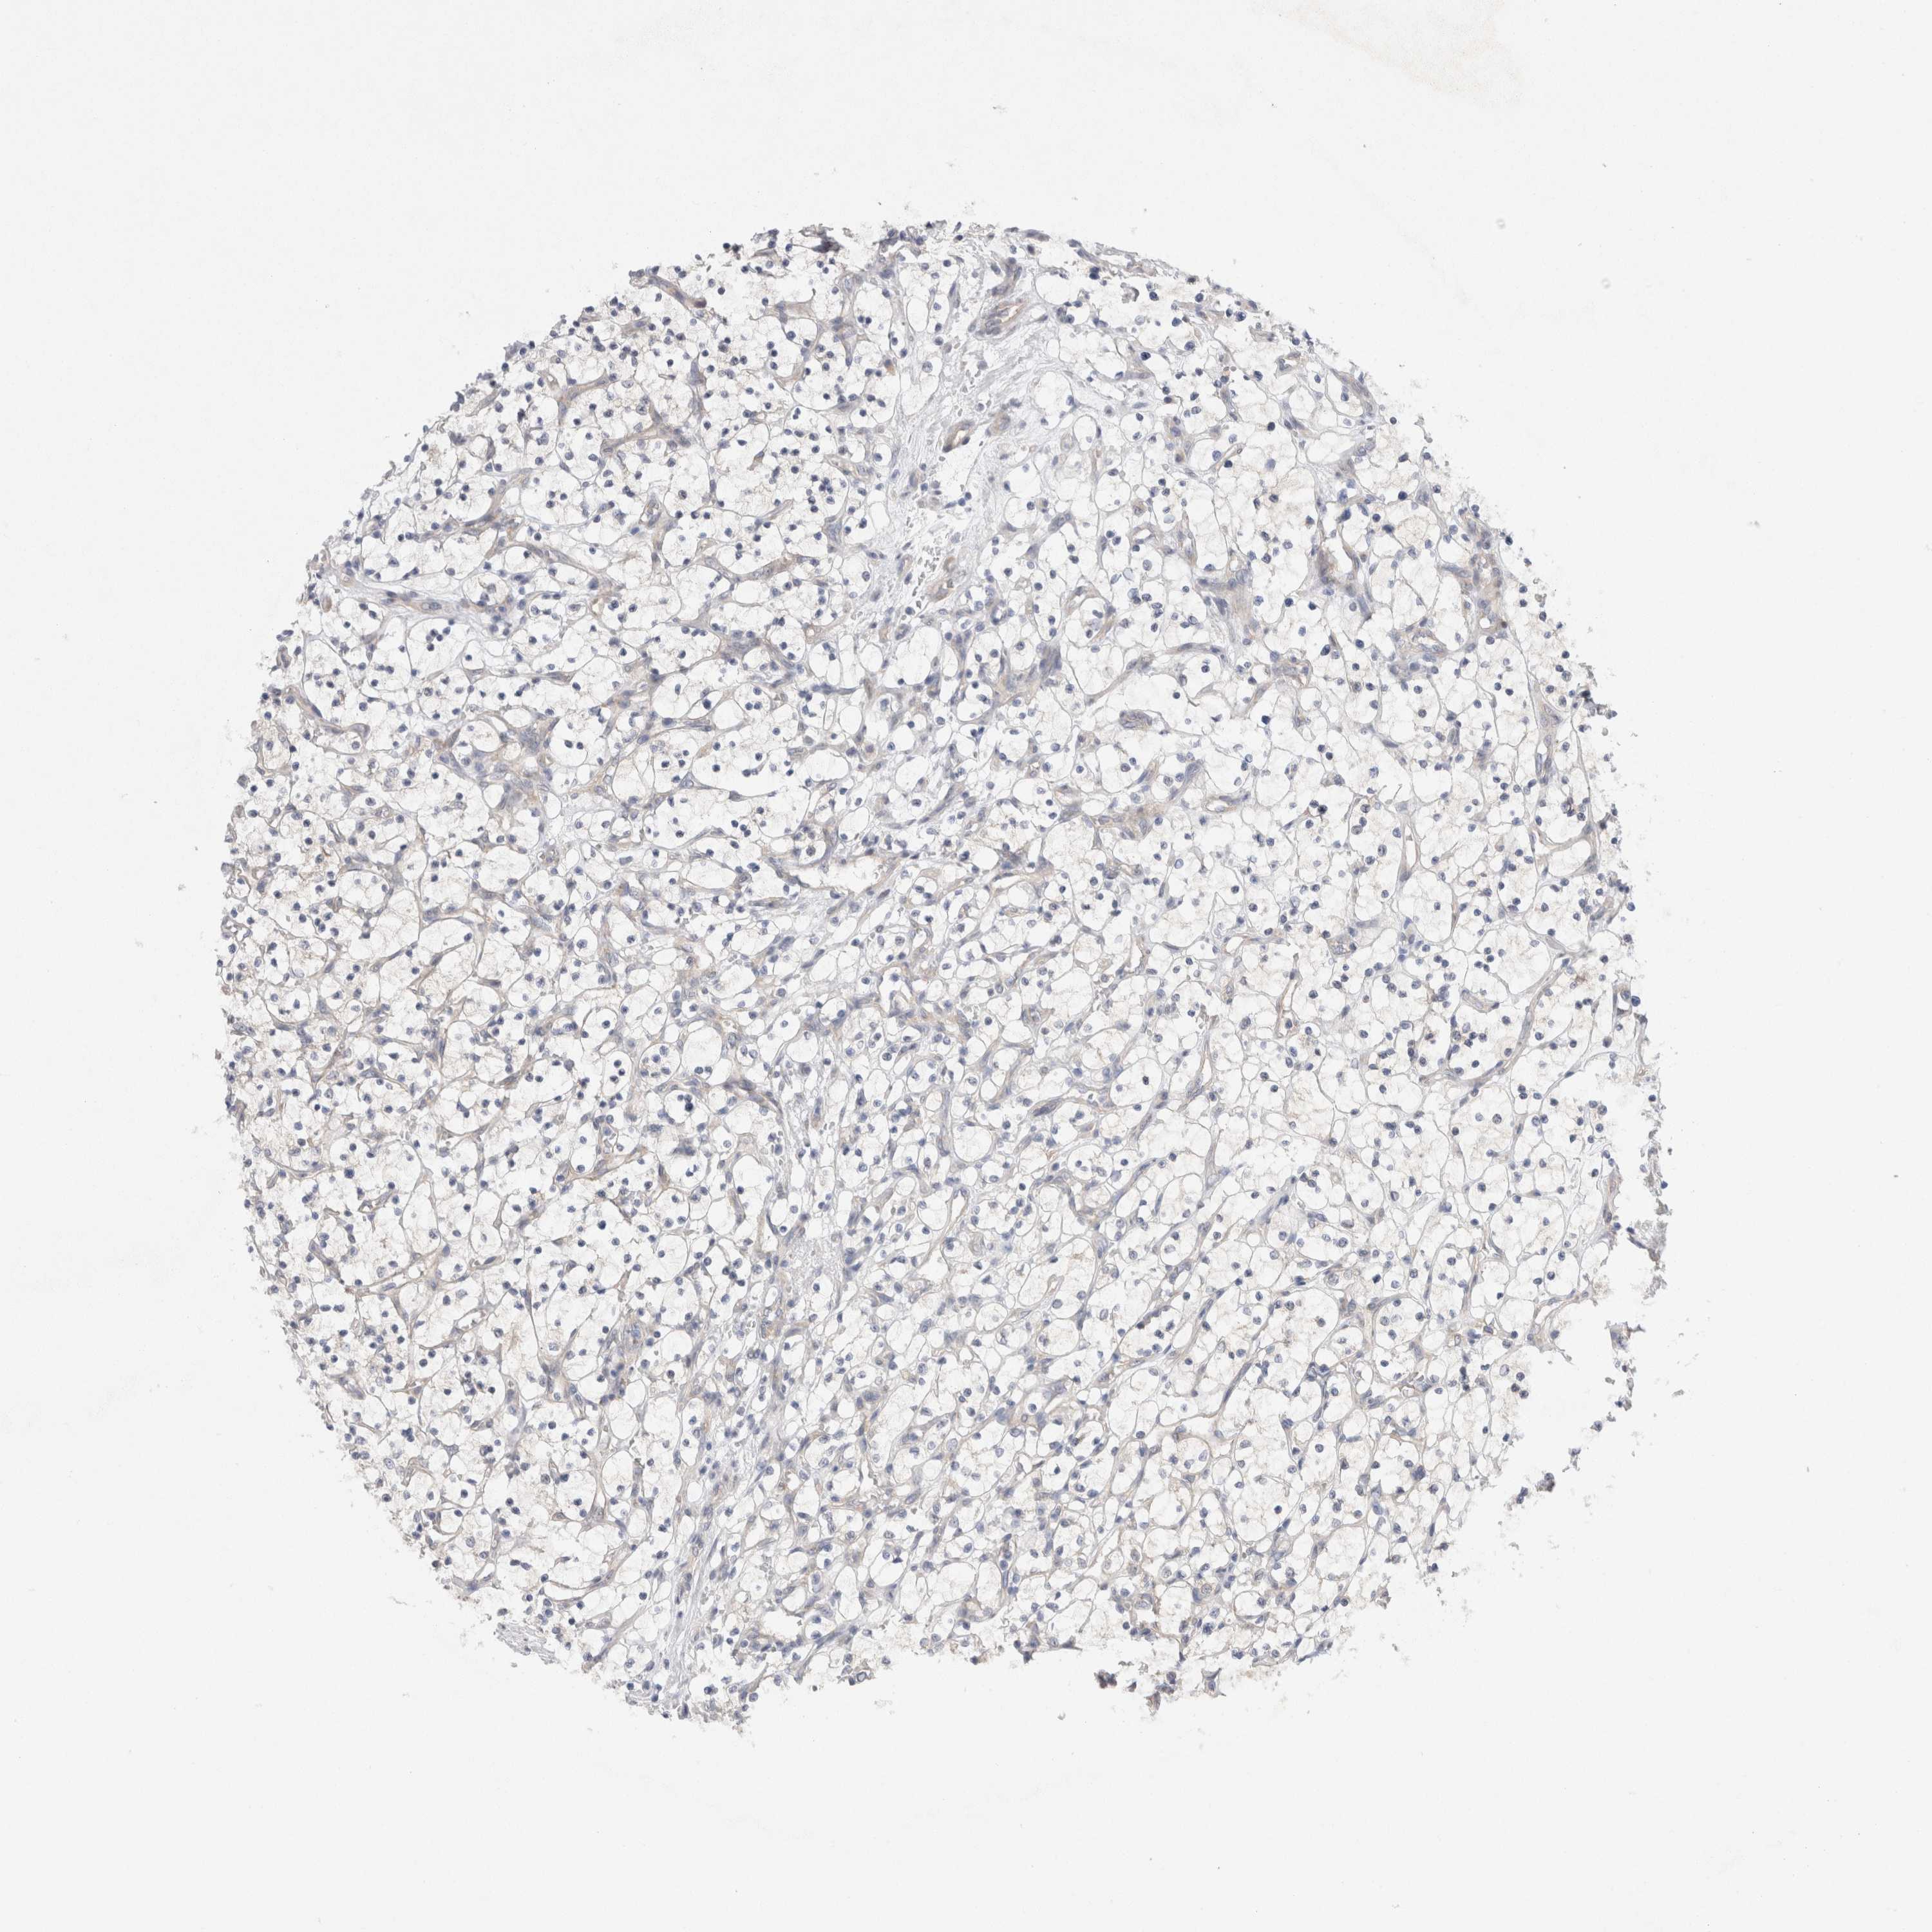

KIDNEY CHROMOPHOBE (TCGA) - Interactive survival scatter ploti

The Survival Scatter plot shows the clinical status (i.e. dead or alive) for all individuals in the patient cohort, based on the same data that underlies the corresponding Kaplan-Meier plots. Patients that are alive at last time for follow-up are shown in blue and patients who have died during the study are shown in red.

The x-axis shows the expression levels (FPKM) of the investigated gene in the tumor tissue at the time of diagnosis. The y-axis shows the follow-up time after diagnosis (years). Both axes are complimented with kernel density curves demonstrating the data density over the axes. The top density plot shows the expression levels (FPKM) distribution among dead (red) and alive patients (blue). The right density plot shows the data density of the survived years of dead patients with high and low expression levels respectively, stratified using the cutoff indicated by the vertical dashed line through the Survival Scatter plot. This cutoff is automatically defined based on the FPKM cutoff that minimizes the p-score. The cutoff can be changed by dragging the vertical line or by entering a cutoff value in the square labeled "Current cut-off".

Under the Survival Scatter plot the p-score landscape (black curve; left axis) is shown together with dead median separation (red curve; right axis). Dead median separation is the difference in median mRNA expression between patients who have died with high and low expression, respectively. It is calculated as follows: median FPKM expression of dead patients with high expression - median FPKM expression of dead patients with low expression. This is intended to aid the user in visually exploring custom cutoffs and the associated p-scores and dead median separation.

Individual patient data is displayed and can be filtered by clicking on one or more of the category buttons on the top of the page. Categories describing expression level and patient information include: high, low, alive, dead, female, male and tumor stages. The scale of the x-axis can be toggled between linear and log-scale by clicking on the "x log" button. Mouse-over function shows TCGA ID, patient information and mRNA expression (FPKM) for each patient.

& Survival analysisi

Kaplan-Meier plots summarize results from analysis of correlation between mRNA expression level and patient survival. Patients were divided based on level of expression into one of the two groups "low" (under cut off) or "high" (over cut off). X-axis shows time for survival (years) and y-axis shows the probability of survival, where 1.0 corresponds to 100 percent.

WIPF2 is potential prognostic, high expression is unfavorable in Kidney Chromophobe (TCGA)

Best expression cut offi

Based on the FPKM value of each gene, patients were classified into two groups and association between prognosis (survival) and gene expression (FPKM) was examined. The best expression cut-off refers the FPKM value that yields maximal difference with regard to survival between the two groups at the lowest log-rank P-value. Best expression cut-off was selected based on survival analysis .

When clicking on this number, the vertical dashed line indicating cut-off, the interactive survival plot, and the Kaplan-Meier curve will be adjusted to show results based on the best expression cut-off.

: 9.48

TCGA RNA samplesi

RNA-seq data is reported as average FPKM (number Fragments Per Kilobase of exon per Million reads), generated by the The Cancer Genome Atlas (TCGA) .

Normal distribution across the dataset is visualized with box plots, shown as median and 25th and 75th percentiles. Points are displayed as outliers if they are above or below 1.5 times the interquartile range. FPKM values of the individual samples are presented next to the box plot.

Average pTPM 11.3

Number of samples 64